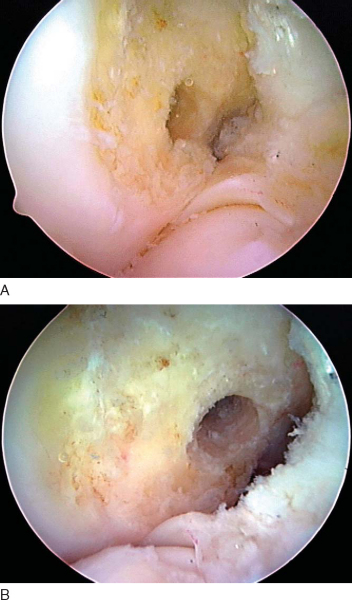

The stability and range of motion of the knee are checked. It is important to verify that the patient has full range of motion before leaving the operating room. The arthroscope is inserted into the knee, and graft tension and impingement are assessed. Our usual graft placement and tensioning technique result in the four strands of the DGST graft being maximally tight between 0 and 20 degrees, with the graft tension decreasing slightly as the knee is flexed to 90 degrees (

Fig. 62-19

). After confirmation that the patient has a full range of motion and negative Lachman and pivot shift test results, the passing and flipping sutures are pulled out of the lateral thigh.